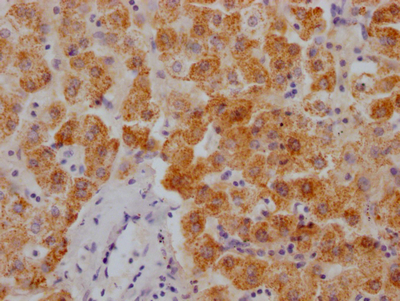

圖片:

應(yīng)用范圍:ELISA, IHC

Application Recommended Dilution IHC 1:20-1:200 -